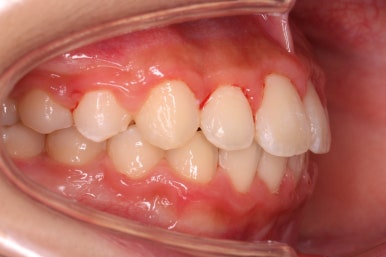

다른 앵글에서의 모습입니다.

안으로 쏙 들어가 있던 앞니가 앞으로 나오게 되면서 심미적으로 좋아지는 것을 볼 수 잇습니다.

삐뚤했었던 특히 안으로 쏙 들어가 있었던 작은 앞니가 개선되면서 웃는 모습이 많이 좋아졌습니다. 상대적으로 덧니처럼 보이던 송곳니의 느낌도 좋아졌네요.

부산비발치교정으로 했음에도 입이 더 튀어나오거나 하지 않았습니다.

옆모습을 보면 치료 후 입술이 조금 튀어나왔나? 싶으시겠지만 치료 전에 억지로 힘을 주며 다물어야 했던 입술이 편하게 다물리면서 그렇게 보이는 것 같고, 실제로 옆에서 웃는 모습을 보면 앞니가 튀어나오거나 하지는 않았습니다.